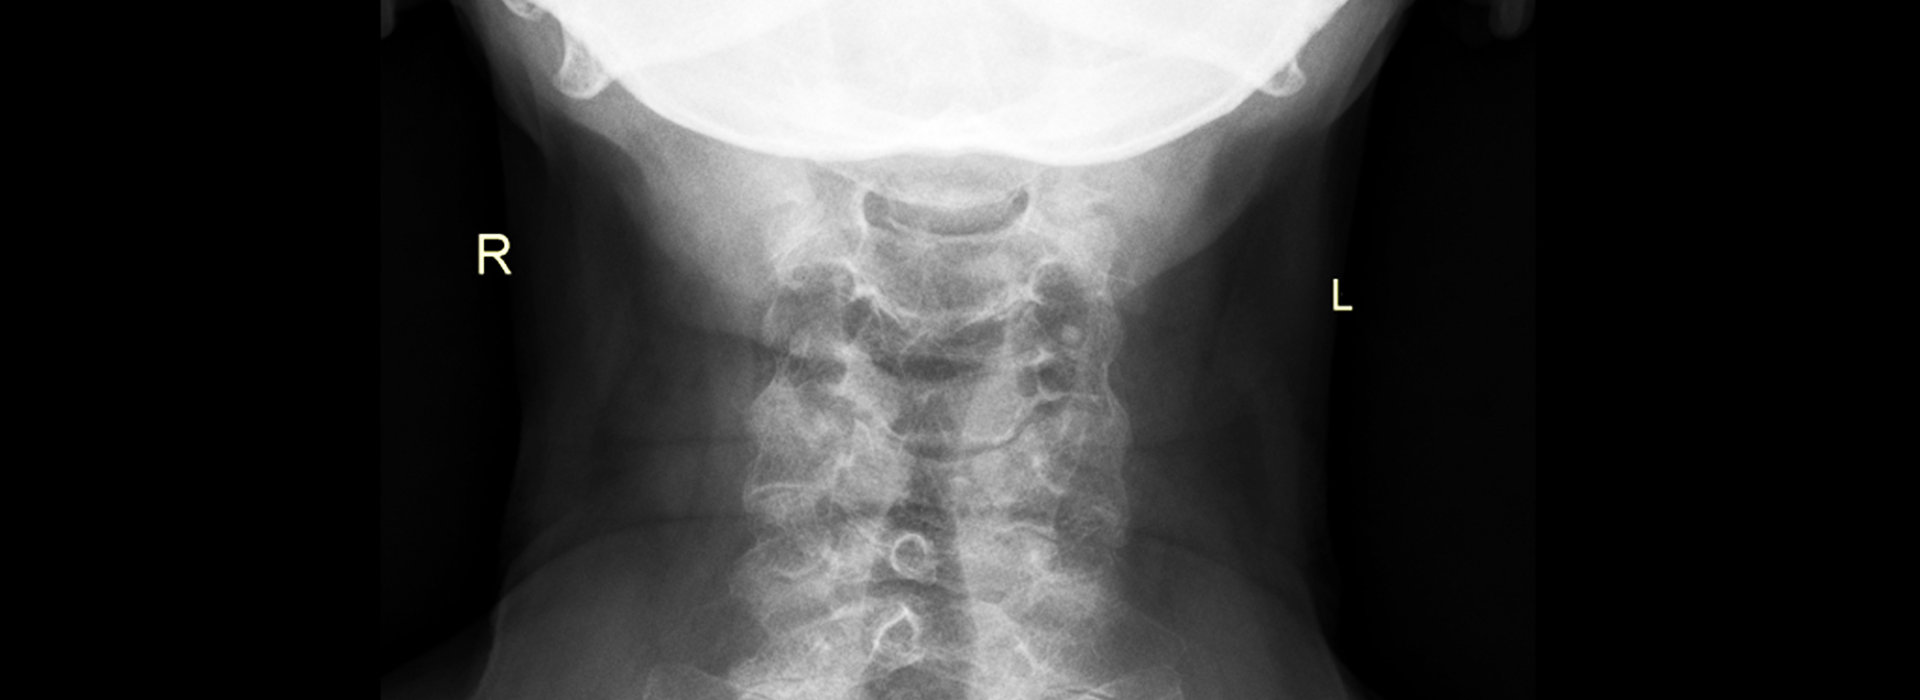

Η πολυετής επικοινωνία μας με, κλινικές, νοσοκομεία, ιατρούς και πελάτεςαπό όλο τον κόσμο, μας έχουν δώσει πολύτιμη εμπειρία και μοναδικό προβάδισμα στην τεχνογνωσία. Με την πάροδο των ετών, οι υπηρεσίες μας στην αντιγραφή και ψηφιοποίηση (scanning) ακτινογραφιών, μαγνητικής και αξονικής τομογραφίας, μαστογραφίας, σπινθηρογραφήματος, αγγειογραφίας, υπερηχοτομογραφίας και κάθε είδους ιατρικής εξέτασης που απεικονίζεται σε φιλμ, έχουν εξελιχθεί σύμφωνα με τις τεχνολογικές απαιτήσεις και συνεχώς εξελίσσονται για να διατηρούν το κορυφαίο επίπεδο ποιότητας και αξιοπιστίας.

- Αντιγραφή Ιατρικών Εξετάσεων

- Ψηφιοποίηση Ιατρικών Εξετάσεων

- Εκτύπωση Ιατρικών Εξετάσεων